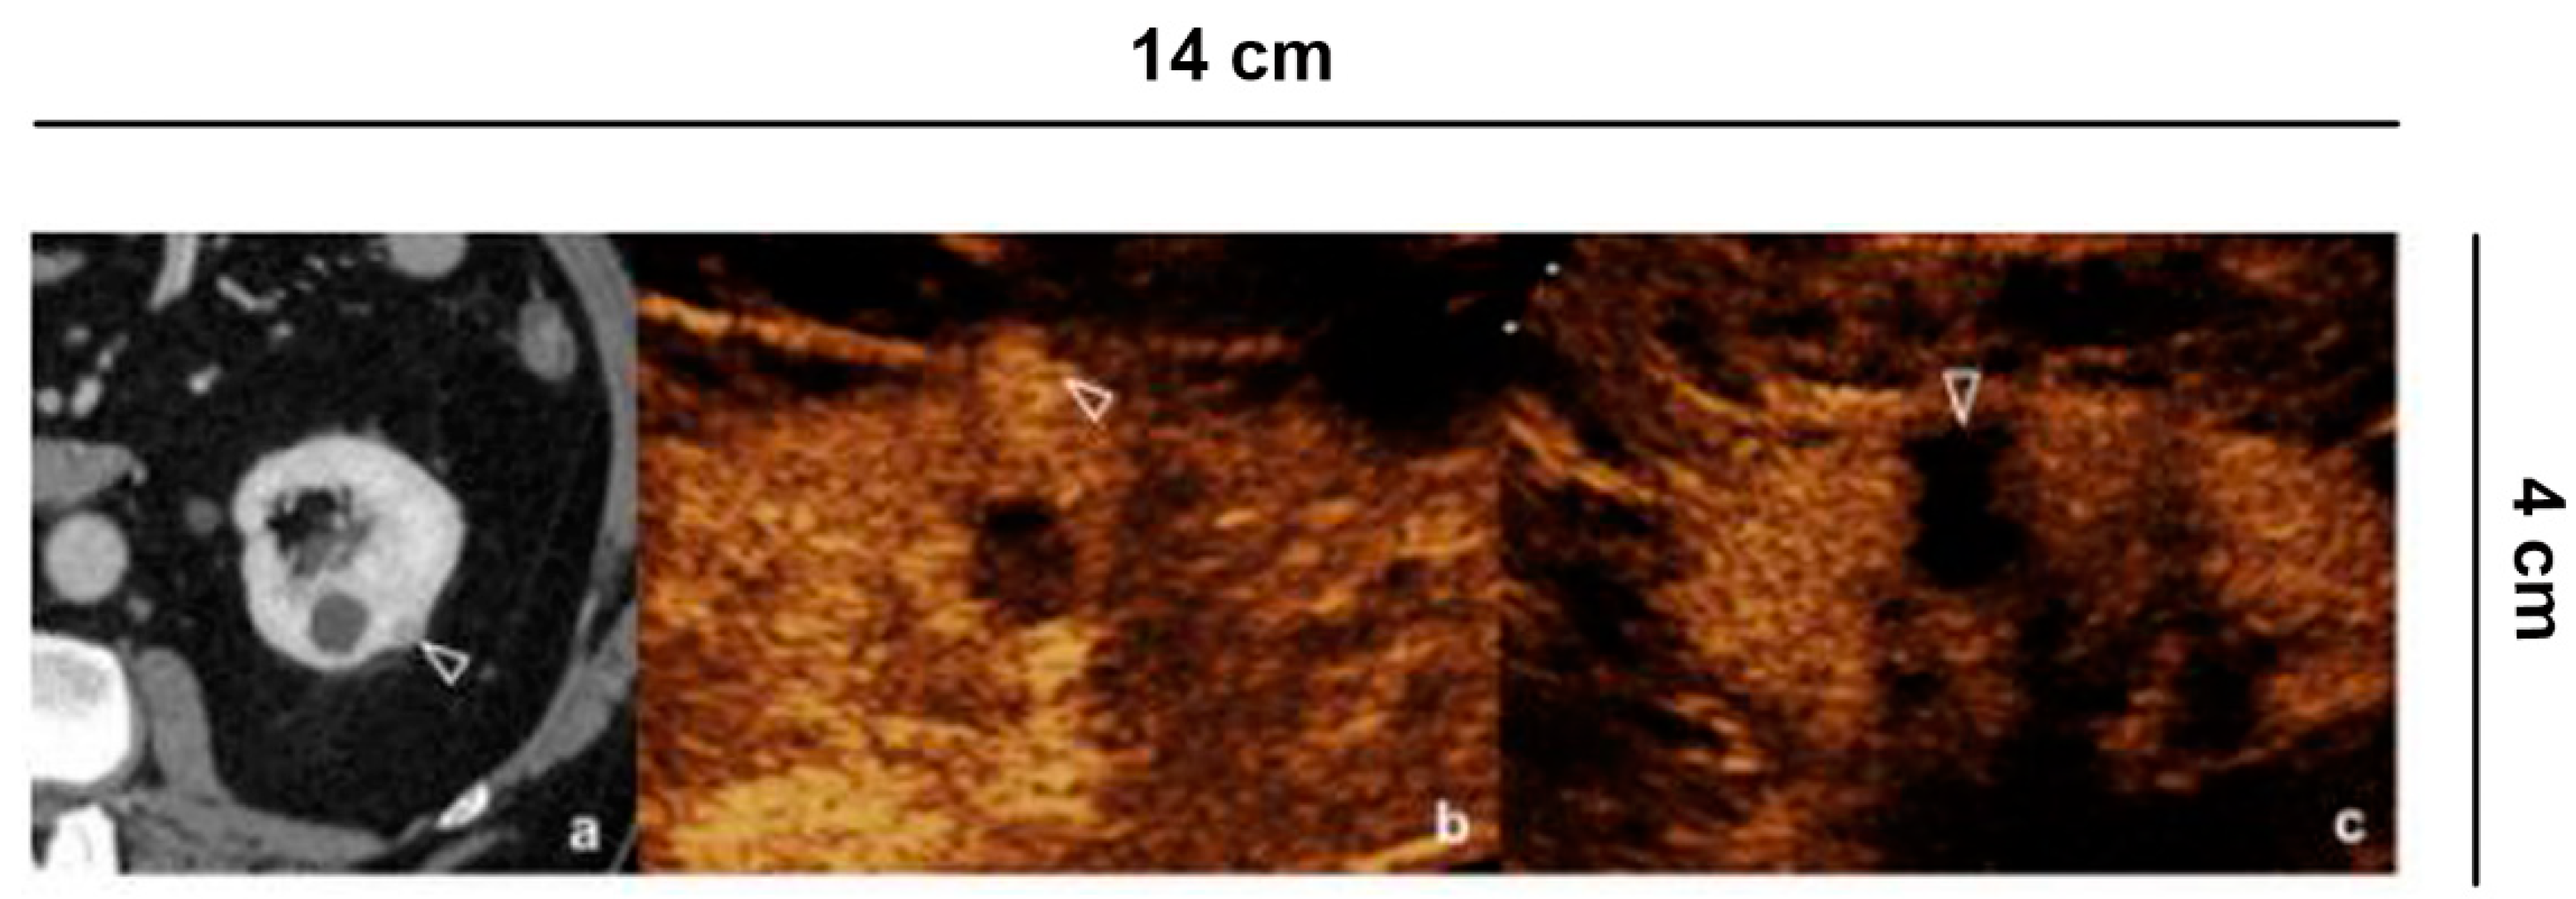

6.5. Follow-Up of Tumor Ablation

In accordance with the EAU guidelines [], evaluation of ablative treatments of small kidney lesions requires a close monitoring of the ablated area, both to check for any complications and to assess the success of the procedure. CEUS has progressively taken a role in the follow-up, especially early after the procedure [,,]. The treatment is considered successful if the lesion becomes completely avascular. This usually occurs early after radiofrequency and microwave ablation (Figure 5) [,], while it may take up to one month after cryoablation (Figure 6), requiring a tailored follow-up [,]. Therefore, an adequate knowledge of the type of ablative treatment allows a correct interpretation of the images, thus reducing the risk of misdiagnosis.

Figure 5.

Follow up of microwave tumor ablation. (a) CECT shows a small renal lesion, partially exophytic, adjacent to a simple cyst, in the middle third of the left kidney; (b) Before the microwave treatment CEUS evidences a hyper-vascular, partially exophytic lesion (arrowheads); (c) After 12 h from the microwave ablation, CEUS shows an avascular area without recognizing the lesion (arrowheads), a sign of treatment success.